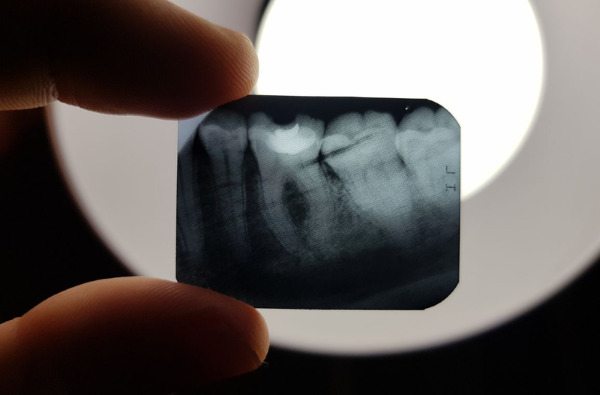

Chụp X quang răng cận chóp (Periapical)

Chụp X quang răng cận chóp là một trong những dạng phổ biến nhất trong nha khoa, nhằm mục đích quan sát chính xác phần chân răng, xương ổ răng và các tổn thương quanh chóp. Loại hình này thường được chỉ định khi khám các vấn đề về nhiễm trùng chân răng, nướu, hoặc xác định độ sâu của sâu răng.

Về mặt chi phí, chụp X quang cận chóp khá phổ biến và có mức giá phù hợp, dao động khoảng 150.000 – 300.000 đồng/lần tùy theo địa điểm. Đặc biệt, nhờ công nghệ hiện đại, hình ảnh chụp rõ nét giúp bác sĩ dễ dàng chẩn đoán chính xác, từ đó đưa ra phương án điều trị tối ưu nhất. Đây là lựa chọn lý tưởng cho những trường hợp cần theo dõi sát tổn thương bên trong.